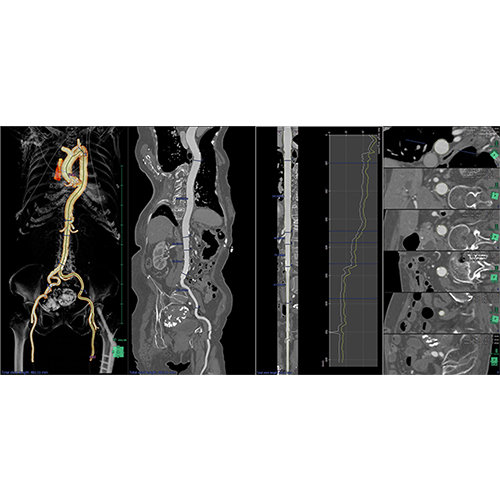

View X-Ray CT & MRI Scans Fast and Easily

Designed for surgeons, Pro Surgical 3D makes it easy to view patient scans quickly. Pro Surgical 3D facilitates the optimal 3D treatment and assessment workflows based on X-ray CT and MRI scans – and best of all, it’s FREE!

Traditional multi-planar slicing

High-quality and fast 3D reconstruction and 3D rendering

Performs 3D reconstruction and volume rendering.

Multi-planar slicing.

Oblique slicing.